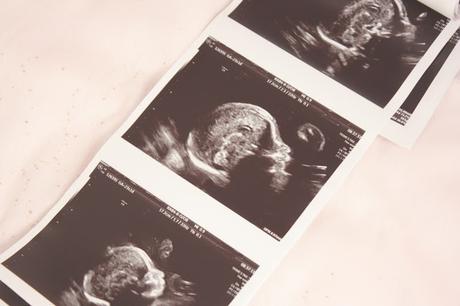

Nous attendions avec impatience ce moment car c'est durant les échographies que nous pouvons vraiment être rassurés que tout se passe bien pour Bébé et parce que comme tout futurs parents (je suppose) voir son bébé en image est un moment très privilégié et tellement magique.

L'échographe regarde comment est positionnée Notre Princesse, elle a bien la tête en bas comme nous l'avait dit la sage-femme le mois précédent. Ensuite il regarde son crâne, ses contours, son cerveau. Il nous montre son visage. On la voit bien, qu'est-ce qu'elle a grandi! Nous ne souhaitions pas d'échographie en 3D si cela n'était pas nécessaire et n'en avons pas eu besoin pour déjà apercevoir les traits de son visage. A ce moment je suis aux Anges! Mais pas pendant longtemps... J'ai été déçu, très déçu de n'avoir vu le visage de ma fille qu'une seconde, voir deux peut-être. L'échographe ne s'est pas du tout attardé, dommage.

Même sur les photos de mon échographie, il n'y en a que trois où l'on voit son visage... Le reste est assez flou pour moi. Je sais qu'elle a grandi qu'on ne peut plus désormais la voir en entière sur écran, mais je ne m'attendais pas à ne presque rien percevoir...